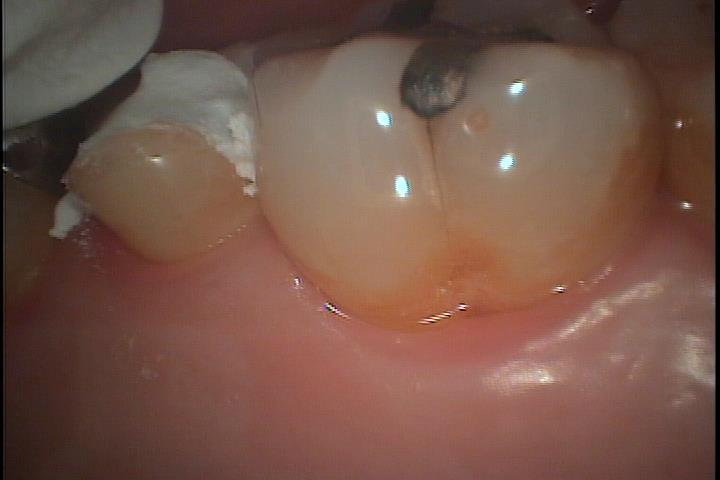

第一大臼歯を側面から見た写真です。

咬合面にアマルガムが確認できます。

その端からクラックが歯肉の方向に走りアマルガムに近い部分はクラックが大きく開き着色しています。